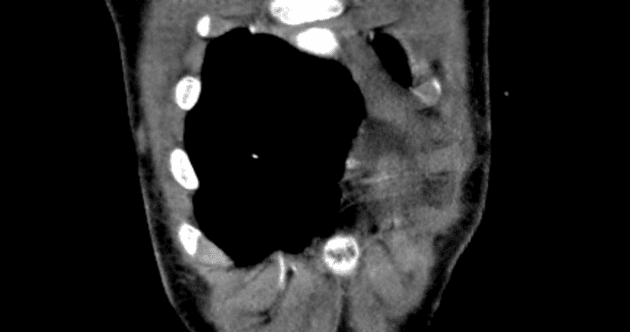

Sagittal thin C+ arterial phase

Chụp cắt lớp vi tính mạch máu động mạch chủ ngực (CT Angiogram Thoracic Aorta):

Chụp có cản quang pha động mạch (sử dụng Omnipaque 350). Không có hình ảnh cắt lớp trước đây để so sánh.

Không thấy tổn thương động mạch chủ do chấn thương hoặc máu tụ trung thất. Ghi nhận thấy ống động mạch còn thông (patent ductus arteriosus).

Tim phải và động mạch phổi không giãn.

- Không tổn thương động mạch chủ do chấn thương. Ống động mạch còn thông có đường kính nhỏ, không có dấu hiệu tăng áp động mạch phổi hoặc phì đại thất phải (RV hypertrophy). Gợi ý hội chẩn với chuyên khoa Tim mạch (Cardiology review suggested).

Ống động mạch (ductus arteriosus) là một mạch máu nối động mạch chủ xuống gần đoạn đầu với phần trần của thân động mạch phổi gần nơi xuất phát của động mạch phổi trái. Bình thường, ống này tự đóng trong vòng 24–48 giờ sau sinh do tăng áp lực oxy và giảm nồng độ prostaglandin. Việc không đóng lại sẽ dẫn đến tình trạng ống động mạch còn thông (patent ductus arteriosus – PDA).

Trong bối cảnh chấn thương, việc phân biệt giữa PDA và tổn thương động mạch chủ do chấn thương là rất quan trọng. Trong trường hợp này, vị trí giải phẫu, không có bất thường thành mạch, cùng với việc không có máu tụ trung thất hoặc các tổn thương ngực đáng kể khác giúp khẳng định chẩn đoán PDA.

Ống động mạch còn thông (Patent ductus arteriosus)